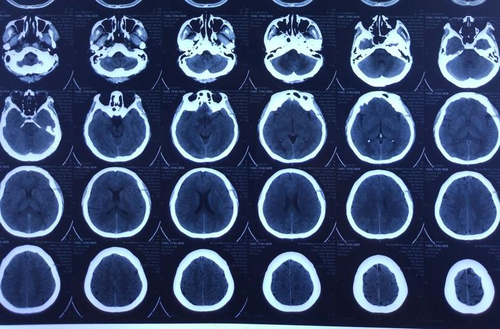

如果是左半边头皮麻的现象,很可能是因为受到了风寒所引起的,这种情况很可能是因为感冒所引起的,如果是左半边脑袋里面发麻的话,这种情况是比较严重的,患者要及时的到医院做详细的检查,及时的了解病情的原因,得到有效的治疗。